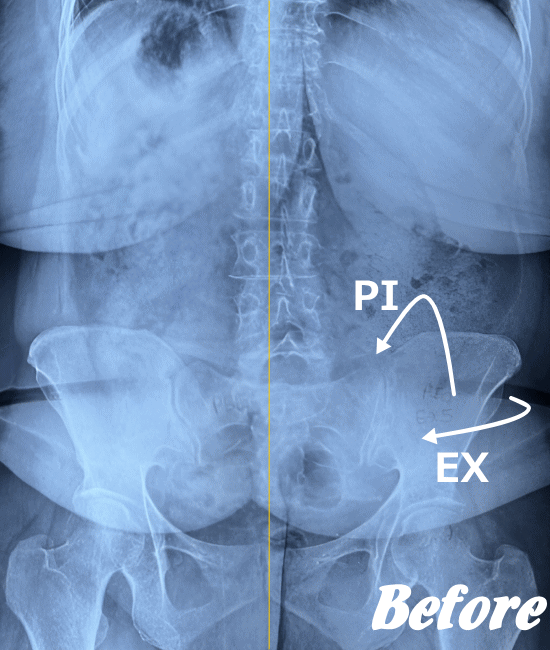

仙骨は仙腸関節が可動することで、呼吸や身体の動きに合わせて、僅かにですが、前屈、後屈、左右回旋…と動きます。ただ、画像検査ではわからない程度の動きです。2~3ミリ程度の可動域だといわれています。

仙腸関節自体はごくわずかな動きしかありませんので、レントゲンやCT、MRIなどでは画像診断で判別することが難しいと言われています。

したがって、画像検査が難しいため、仙腸関節障害の診断は、症状経過と仙腸関節部の圧迫テストで診断されます。

HALOカイロプラクティック☆平和島整体院では、仙腸関節の動きやズレを回復させることを第一に考慮した施術を行っています。たとえ、足や肩の痛みやしびれが主訴であっても、仙腸関節を正しい状態に戻すことから施術を始めています。

仙腸関節、股関節、脊柱を特に集中して解剖学的に正しい位置へと戻す施術になります。HALOカイロプラクティック☆平和島整体院では、医療機関でも用いられているAKA療法も取り入れて施術しています。